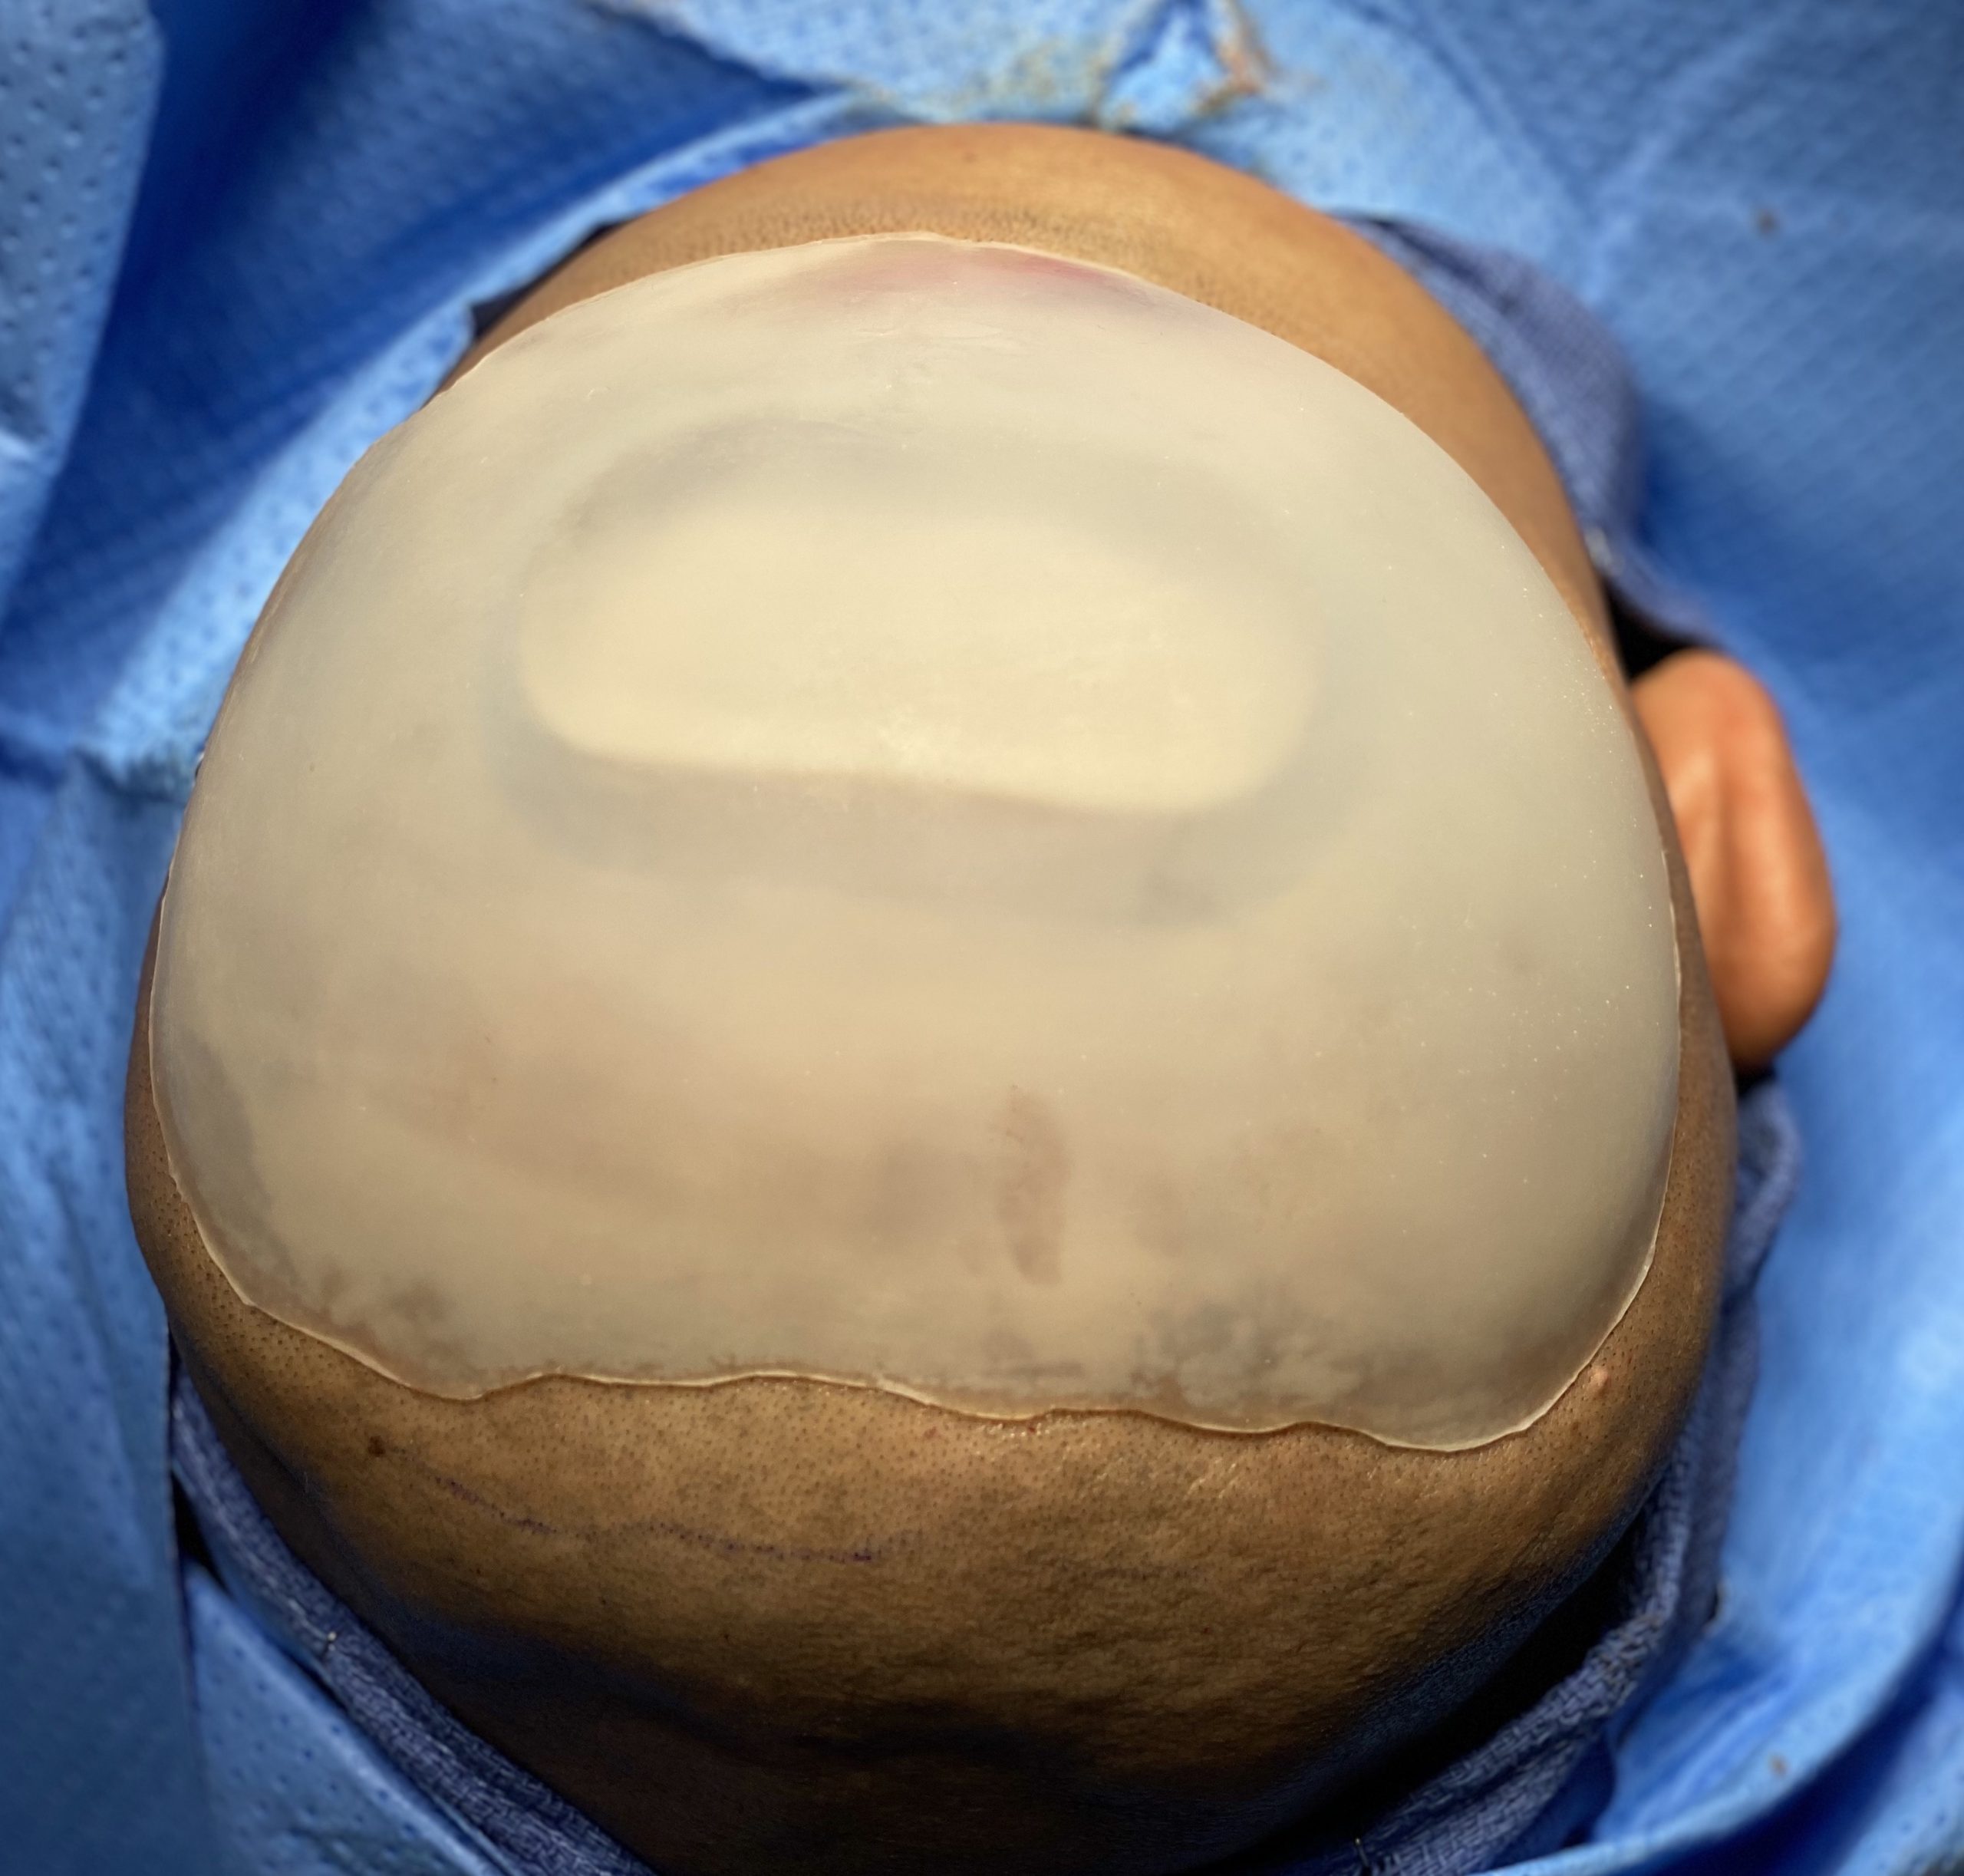

Patient 51

Desire for taller and rounder head shape.

Two stage custom skull implant augmentation technique.

Desire for taller and rounder head shape.

Two stage custom skull implant augmentation technique.